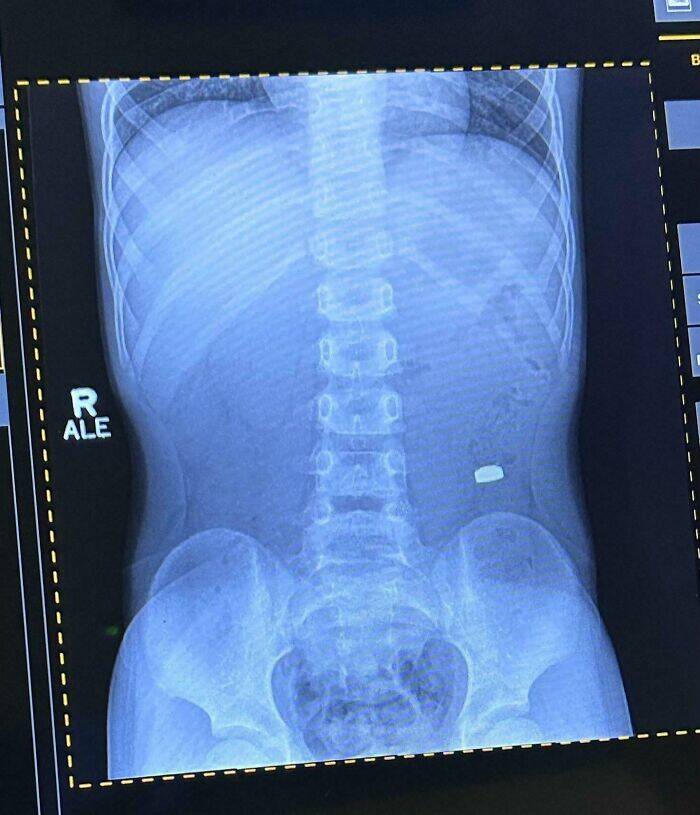

My Son Ate A Battery

Proof That Parenting Is Just Controlled Chaos